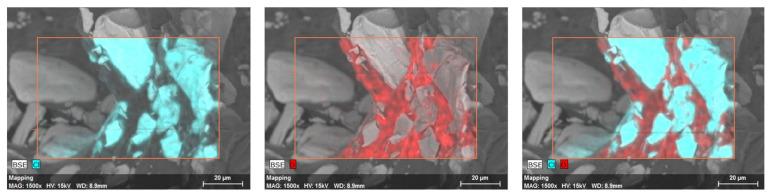

Gastroretentive systems may overcome problems associated with incomplete drug absorption by localized release of the API in the stomach. Low-density drug delivery systems can float in the gastric content and improve the bioavailability of small molecules. The current publication presents verapamil-HCl-containing solid foam prepared by continuous manufacturing. Production runs were validated, and the foam structure was characterized by micro-CT scans and SEM. Dissolution properties, texture changes during dissolution, and floating forces were analyzed. An optimized formulation was chosen and given orally to Beagle dogs to determine the pharmacokinetic parameters of the solid foam capsules. As a result, a 12.5 m/m% stearic acid content was found to be the most effective to reduce the apparent density of capsules. Drug release can be described by the first-order model, where 70% of verapamil dissolved after 10 h from the optimized formulation. The texture analysis proved that the structures of the solid foams are resistant. Additionally, the floating forces of the samples remained constant during their dissolution in acidic media. An in vivo study confirmed the prolonged release of the API, and gastroscopic images verified the retention of the capsule in the stomach.

胃滞留系统可以通过在胃中局部释放活性药物成分(API)来克服与药物吸收不完全相关的问题。低密度药物递送系统可以漂浮在胃内容物中,提高小分子的生物利用度。当前的出版物介绍了通过连续制造制备的含盐酸维拉帕米的固体泡沫。对生产批次进行了验证,并通过微型计算机断层扫描(micro-CT)和扫描电子显微镜(SEM)对泡沫结构进行了表征。分析了溶出特性、溶出过程中的质地变化和漂浮力。选择了一种优化的制剂并口服给予比格犬,以确定固体泡沫胶囊的药代动力学参数。结果发现,12.5 m/m%的硬脂酸含量对于降低胶囊的表观密度最为有效。药物释放可以用一级模型来描述,优化制剂中70%的维拉帕米在10小时后溶解。质地分析证明固体泡沫的结构具有抗性。此外,样品在酸性介质中的溶出过程中漂浮力保持恒定。体内研究证实了API的长效释放,胃镜图像验证了胶囊在胃中的滞留情况。